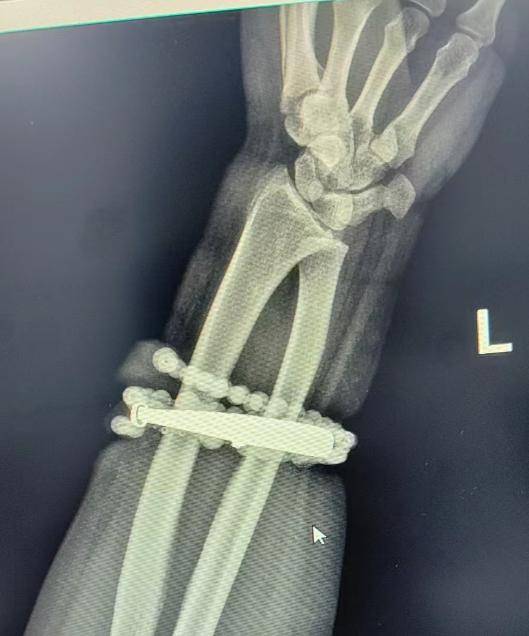

皇冠登3代理出租(9990088.com)-开会_员平_台出租)皇冠信用网/如何开户-占成_代理(登1登2代理登3(足球平台)戴了十年没摘的手镯、串珠竟长进了肉里,还发炎了!近日,福建省宁德市闽东医院创伤骨科、手显微外科就接诊了这样一位患者登1信用盘代理 。

33岁的龚女士(化名)手腕上的银手镯和串珠戴了近十年,几乎从未摘下来过登1信用盘代理 。随着时间推移,龚女士的体重也有所增加,手腕逐渐被勒得紧绷,但她并未在意。

直到近半年,龚女士手腕的皮肤出现反复瘙痒、发红,以为是普通皮炎,便自行买药膏涂抹登1信用盘代理 。

然而,就在两周前,龚女士的情况急转直下:手腕不仅疼痛加剧,还出现了明显的红肿,甚至有脓液渗出登1信用盘代理 。她这才惊觉——手镯和串珠,已经有一部分“长”进了肉里,根本取不下来了!

“这是典型的首饰长期压迫、摩擦,加上细菌感染,引发的慢性炎症和肉芽组织增生登1信用盘代理 。”医生介绍,此时,手镯和串珠已经成了一个不断刺激皮肤、污染伤口的“病灶”,如果不尽快手术取出,感染可能进一步扩散,甚至危及生命或影响手臂功能。

经过一个多小时的手术,医生们将手镯和串珠从厚厚的增生组织中完整剥离出来登1信用盘代理 。目前,龚女士恢复良好,已顺利出院。